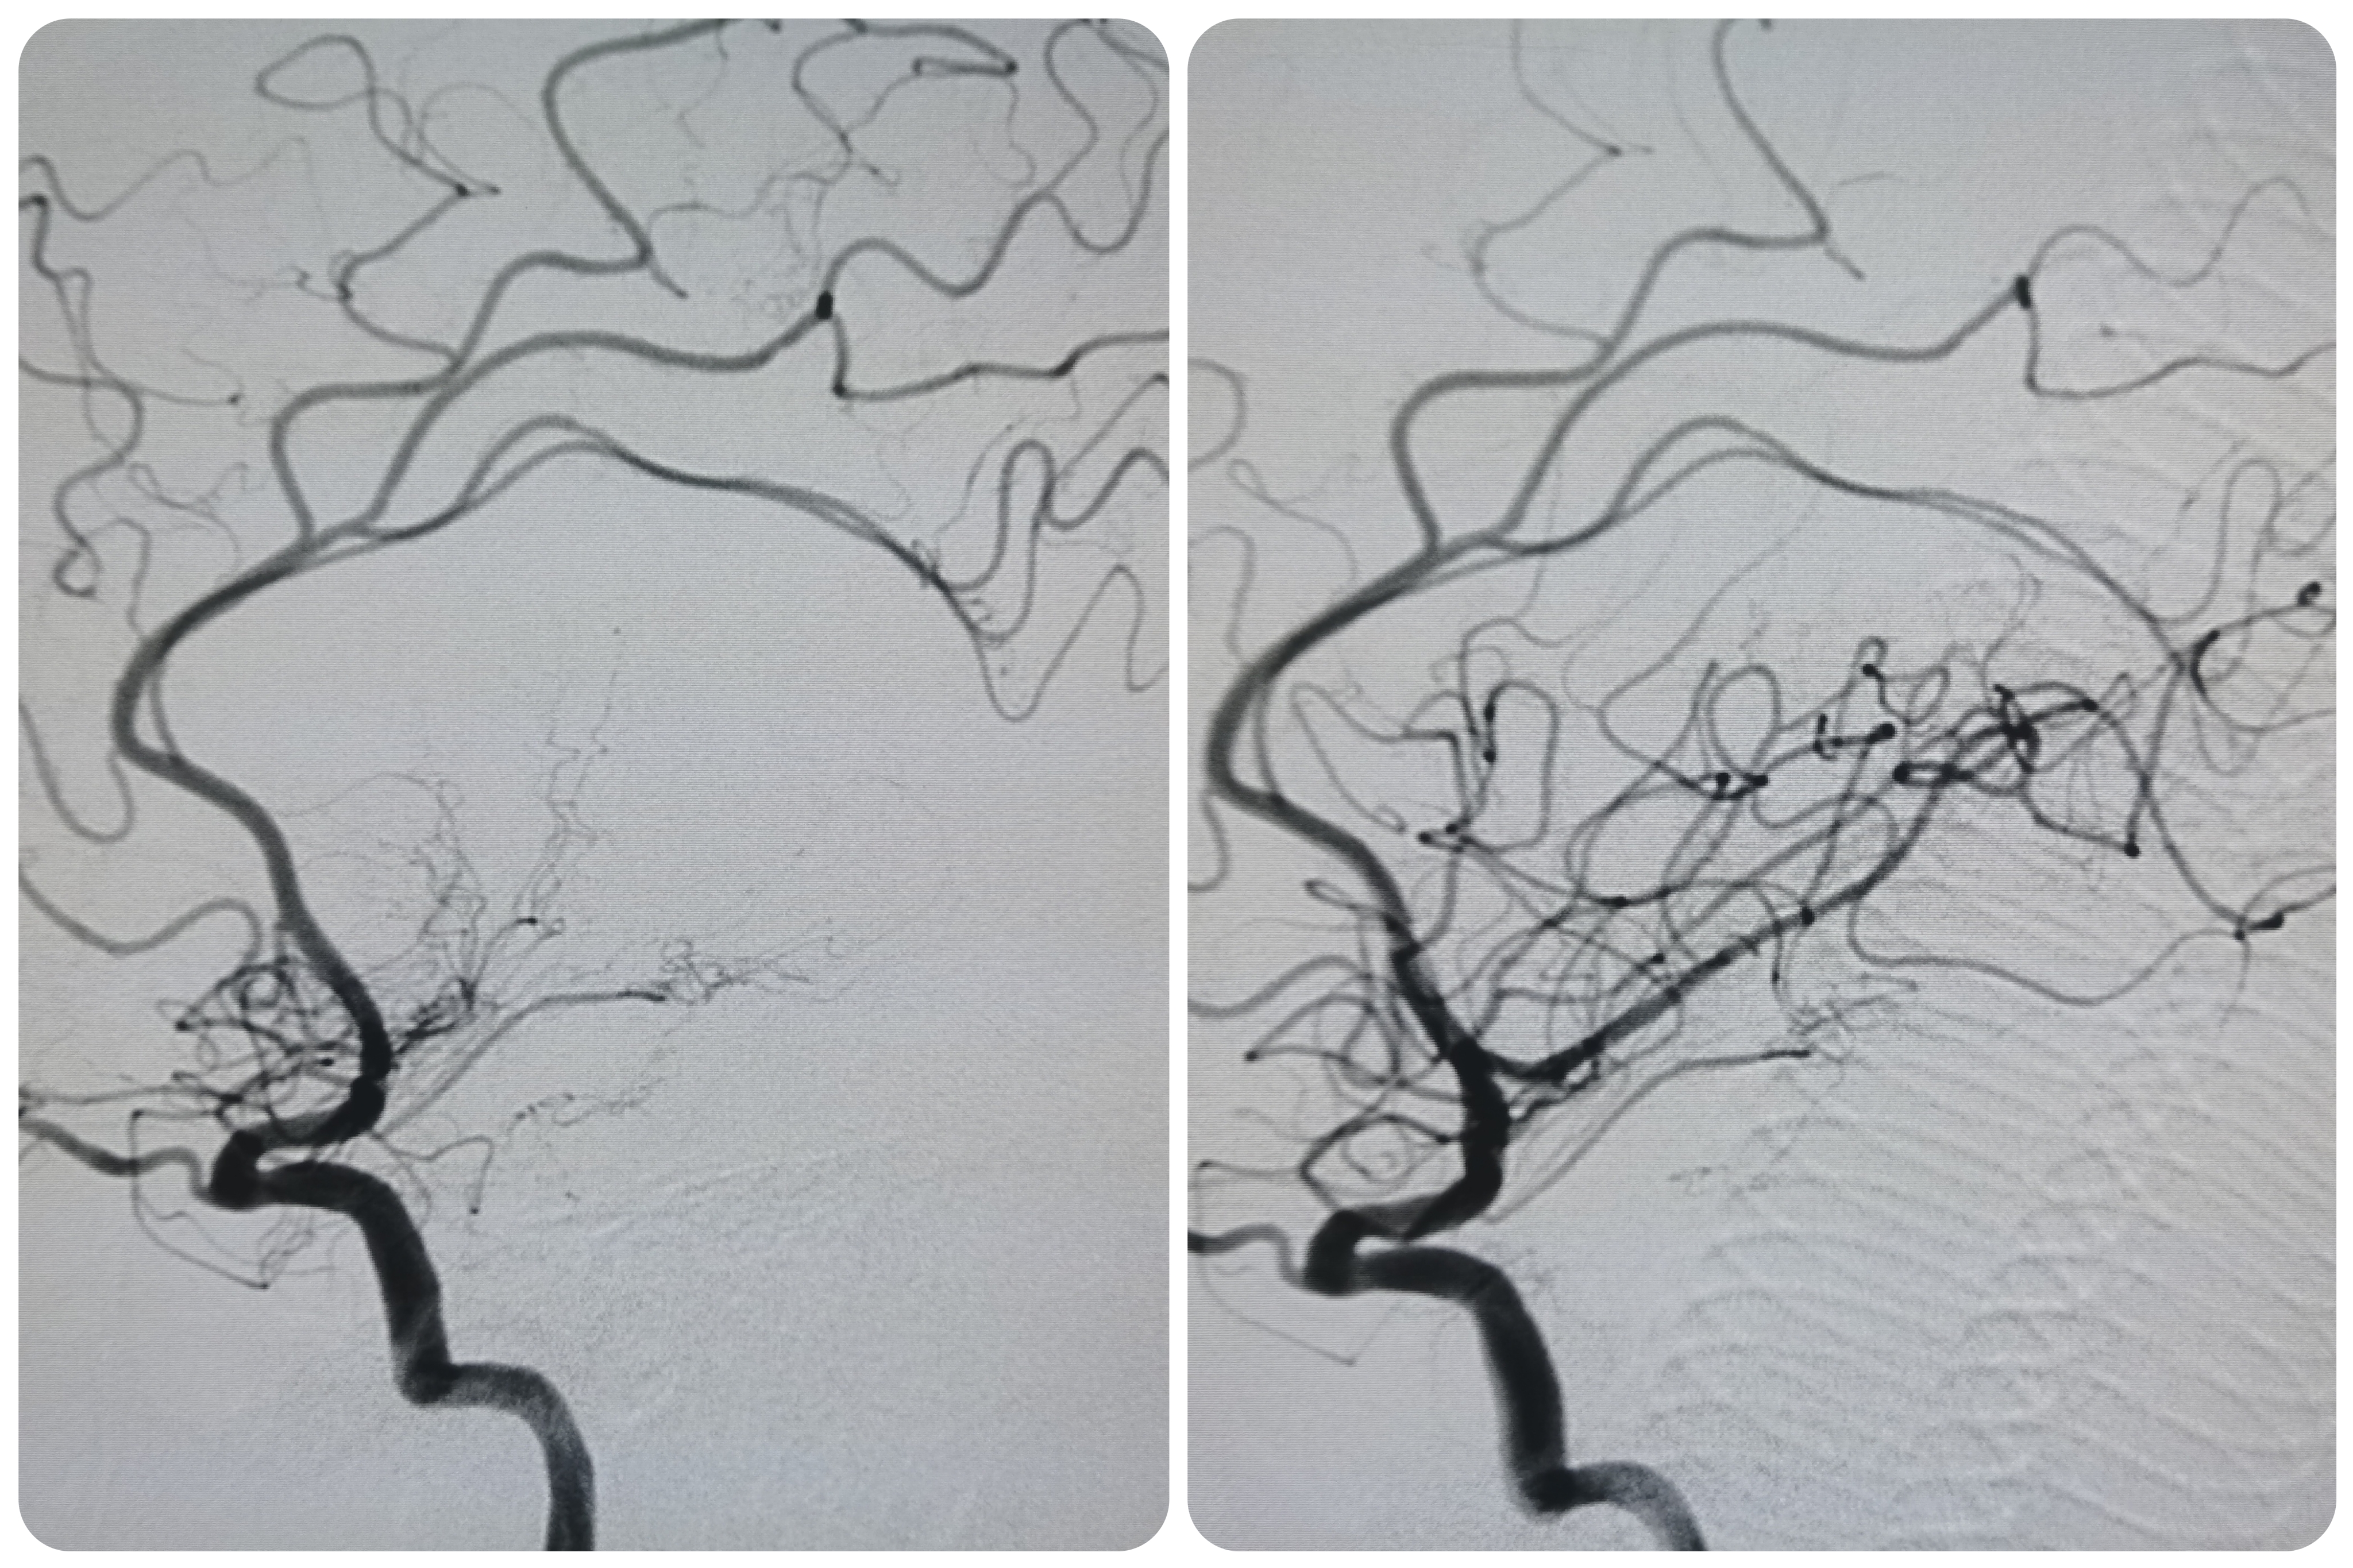

复查造影见颅内狭窄解除,血流通畅,遂未再植入支架,撤出导丝及各级系统,结束手术。患者麻醉苏醒顺利,无新发神经系统症状,给予替罗非班持续泵入,监测生命体征,控制血压避免再灌注损伤。

术前术后对比